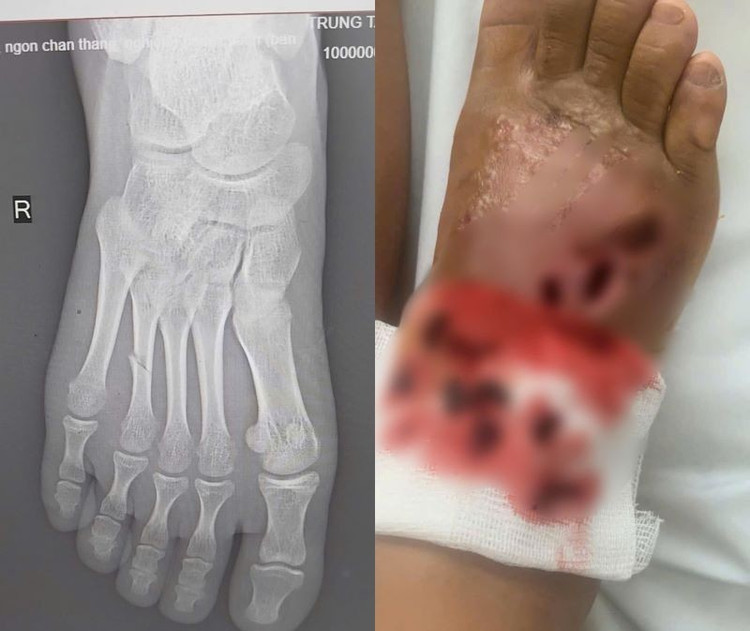

Trung tâm Y tế huyện Đoan Hùng (Phú Thọ) vừa tiếp nhận bệnh nhi N. T. T. T., 14 tuổi, ở Sơn Dương, tỉnh Tuyên Quang, trong tình trạng bàn chân phải sưng nề, đau nhức dữ dội, có nhiều ổ loét sâu đang hoại tử, dịch mủ chảy ra và có dấu hiệu nhiễm trùng lan rộng sau khi tự điều trị bằng phương pháp bó thuốc nam tại nhà.

Chỉ sau 5 ngày, vết thương đã bắt đầu sưng to, đau nhức dữ dội, chảy dịch mủ và có mùi hôi. Sau khi thấy triệu chứng tiến triển nặng hơn, gia đình đưa cháu tới khám tại Trung tâm Y tế huyện Đoan Hùng.

Chân hoại tử do đắp lá chữa gãy xương - Ảnh BVCC

Tại đây, sau khi thăm khám lâm sàng và cận lâm sàng, kết quả trên phim chụp X-Quang cho thấy hình ảnh bị gãy xương đốt bàn chân/nhiễm trùng nặng bàn chân phải.

Các bác sĩ đã loại bỏ ổ nhiễm trùng, điều trị kháng sinh liều cao cho bệnh nhi, bó bột hở vị trí loét. Sau 1 tuần điều trị, tình trạng nhiễm trùng được cải thiện, sức khỏe bệnh nhi ổn định.